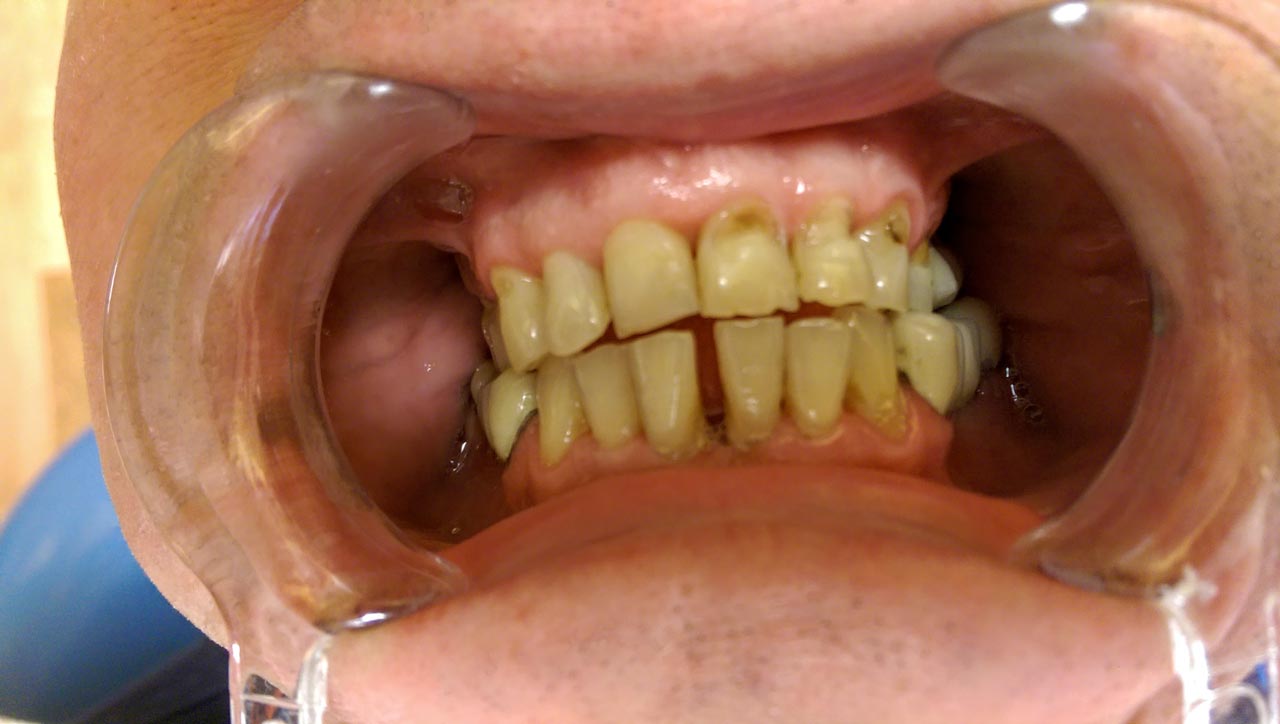

Alsó állcsont teljes rehabilitációja 72 óra alatt, azonnal terhelhető implantátumokkal súlyos paradontitisben szenvedő dohányzó páciens esetében. Az alsó állcsont fogai mind mozogtak az előrehaladott fogágypusztulás miatt.

A fogakat eltávolítottuk, a gyulladt, fertőzött csontot kitakarítottuk, kifertőtlenítettük, majd azonnal implantáltunk.

Svájci, IHDE márkájú, azonnal terhelhető implantátumokat helyzetünk be, és ezekre harmadnapra rögzített, hosszútávú, fémvázas, esztétikus műanyaggal leplezett hidat ragasztottunk be.

Ezt az ideiglenes hidat a sebek gyógyulása miatt használjuk, de tartóssága miatt véglegesként is használható. A legtöbb esetben, ahogy itt is, 6 hónap múlva porcelán hídra cseréljük, a teljes gyógyulás után.